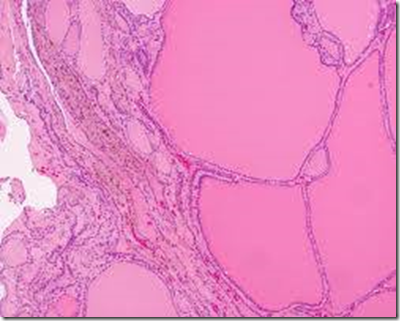

Tx for a colloid nodule dx by thyroid FNA

Thyroid suppression only